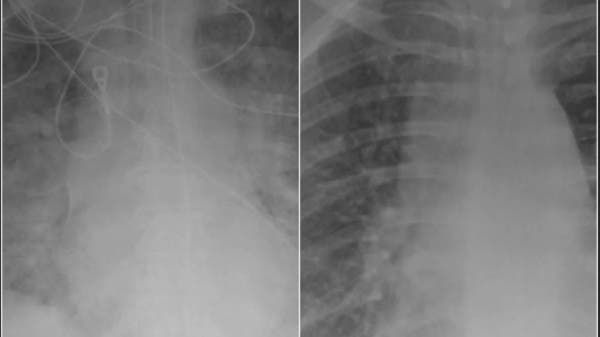

وتظهر صورتان بالأشعة السينية التأثيرات المختلفة للفيروس على الرئتين بين شخصين مصابين بكوفيد-19، ولكن واحدة تعود لشخص تم تطعيمه بلقاح مضاد لفيروس كورونا، والثانية ترتبط بمريض لم يتلقَ اللقاح.

رئتا مريض كورونا لم يتلق اللقاح

وأوضح الدكتور كامل أن اللون الأبيض الذي نراه في رئتي الشخص غير الملقح هو الضرر الذي يسببه الفيروس. وقد يكون ذلك عبارة عن بكتيريا أو مخاط أو إفرازات، مؤكداً أن المريض غير الملقح الذي شوهد في صورة الأشعة السينية يحتاج على الأرجح إلى رعاية كبيرة.

وبحسب تقرير الصحيفة، فمن المؤكد أن ذلك المريض سيحتاج على الأقل إلى الأكسجين وأحياناً قد يحتاج إلى أكثر من ذلك. وقال كامل: "قد يحتاج هؤلاء المرضى إلى جهاز التنفس الصناعي أو التهوية الميكانيكية والتخدير ودعم الحياة بشكل أساسي". وأضاف أن الرئة السليمة المليئة بالهواء تحتوي على مناطق سوداء أكثر في صور الأشعة السينية.

رئتا مريض كورونا تلقى اللقاح

وتعد صورة الأشعة السينية للشخص الذي تم تطعيمه والمصاب بفيروس كورونا حالة اختراق نادرة، فقد أصيب أقل من 1% من الأشخاص الذين تم تلقيحهم، وأولئك الذين يصابون في أغلب الأحيان لديهم أعراض خفيفة وقد لا يحتاجون للذهاب إلى المستشفى. ولا يعاني البعض من أي أعراض أو قد يشعرون وكأنهم مصابون بنزلة برد عادية.

وأوضح كامل أن معظم الذين يتم تطعيمهم وينتهي بهم الأمر بالذهاب إلى المستشفى لا يحتاجون إلى نقلهم إلى وحدة العناية المركزة أو وضع أجهزة الإنعاش، لكن الاستثناءات تشمل أولئك الذين لديهم أمراض موجودة مسبقاً أو الذين يعانون من نقص المناعة.